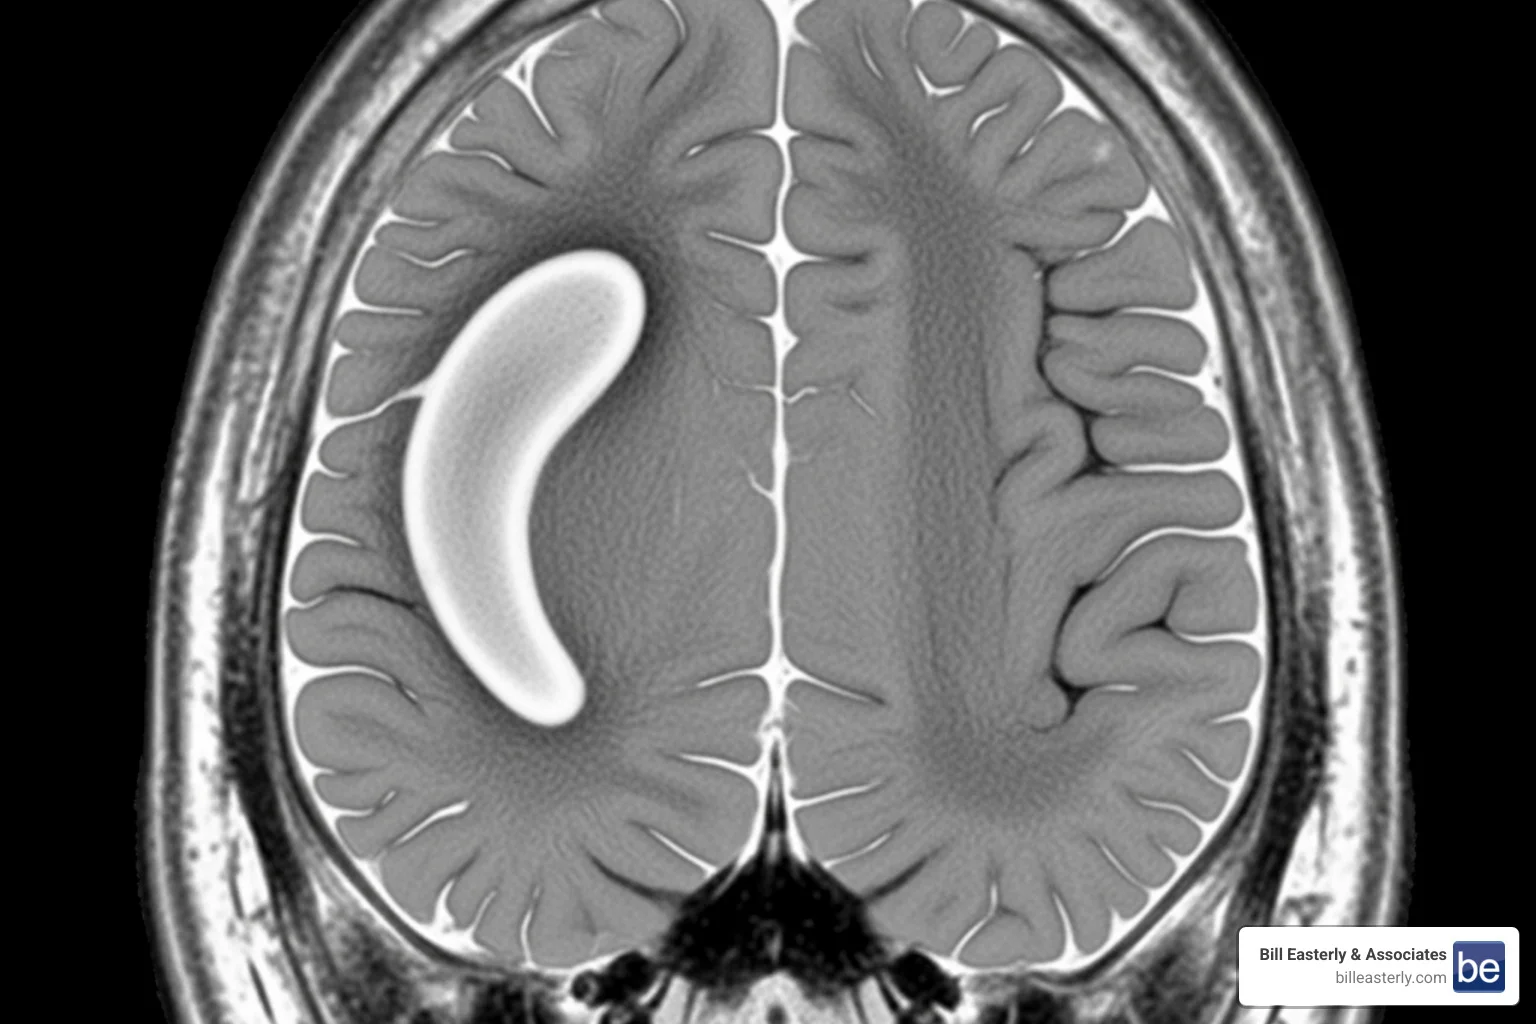

Brain scan showing a subdural hematoma - Motorcycle accident brain injury

• Hematoma: A collection of blood or clot that puts pressure on the brain. An epidural hematoma forms between the skull and the brain’s outer layer, while a subdural hematoma forms underneath that layer. Both are extremely dangerous.